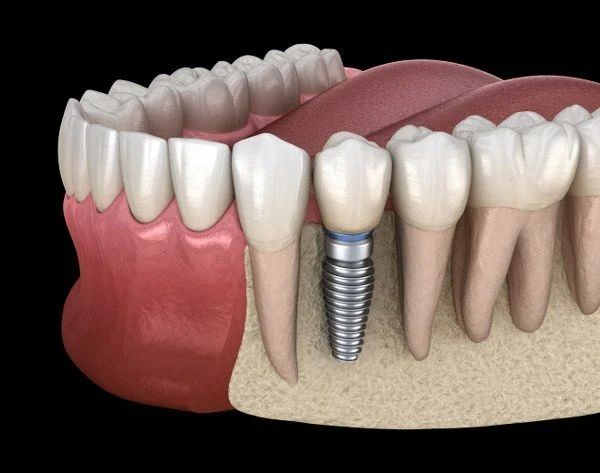

3 BENEFÍCIOS DOS IMPLANTES FEITOS AQUI

Uma equipe multidisciplinar planeja e executa o procedimento, garantindo diagnóstico preciso e o tratamento ideal para seu sorriso. Conheça as etapas.

1. Estabilidade Funcional

Implantes fornecem suporte firme para mastigação eficiente, evitando soluções frágeis como próteses móveis.

2. Preservação Óssea

Afixação direta ao osso reduz perda óssea progressiva e mantém a estrutura facial.

3. Durabilidade elevada

Materiais resistentes oferecem longa vida útil, diminuindo retrabalhos e custos futuros.

O que é um Implante Dentário?

Implante dentário é uma raiz dental artificial instalada no osso maxilar, pelo Implantodontista. Contudo a cirurgia é pouco invasiva, e repõe melhor um dente perdido, ou até a arcada completa.

A Implantodontia permite portanto realizar melhores tratamentos para colocar um dente ou vários dentes, bem como para a arcada completa em um implante total com carga imediata para a reabilitação oral de todos os dentes.

Na Ferst Odontologia, os implantes dentários são realizados com planejamento cuidadoso e tecnologia moderna para devolver a função e a estética do sorriso. Os implantes substituem dentes perdidos de forma segura e eficiente, proporcionando mais conforto, firmeza na mastigação e um resultado natural.